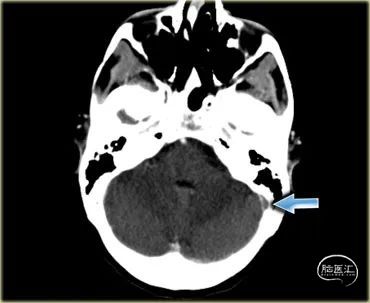

下图 一位颞叶出血患者的图像。

当梗死的出血性成分很大时,它可能看起来就像任何其他伴有血管源性水肿的脑内血肿。

这个病例的诊断线索是在增强图像上看到的,它很好地显示了乙状窦的充盈缺损(蓝色箭头)。

下图 有血管源性水肿(红色箭头),细胞毒性水肿和出血(蓝色箭头)。

这些发现和位于颞叶的位置,应该会让你想到由Labbe静脉血栓所致的静脉梗塞。下一次检查应该是增强的MR或CT,以证明诊断。